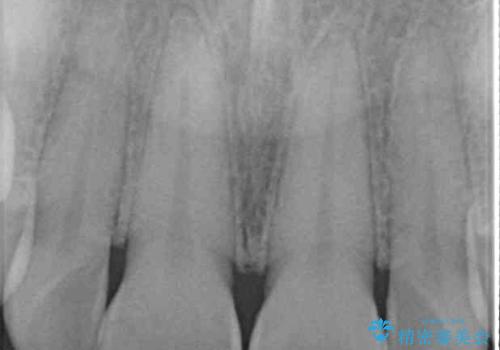

転んで欠けてしまった前歯 オーダーメイドのオールセラミッククラウン

- 転んで欠けてしまった前歯を気にして来院された患者様です。

転んだ際に歯の先端1/4ほどが欠けてしまい、近医にて修復をしてもらったとのことですが、将来的にオールセラミッククラウンを装着する可能性を説明されたため、当院にて補綴治療を行うこととしました。

オーダーメイドタイプのセラミッククラウンは、既製タイプのク色のラウン(スタンダードタイプ)とは異なり、色合いが合うまで何度も修正を行って調整をいたします。